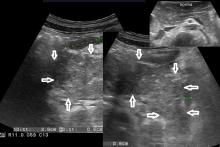

Rozpoznanie: W badaniu usg - trzustka pogrubiała, obrzęknięta (strzałki), przewód trzustkowy nieposzerzony (dla porównania na zdjęciu w górnym prawym rogu - prawidłowa trzustka u innego pacjenta). W badaniu TK (poniżej) - trzustka powiększona, niejednorodna, słabo odgraniczona od otoczenia, po podaniu kontrastu jedynie głowa fragmentarycznie na wysokości wyrostka haczykowatego ulega wzmocnieniu kontrastowemu, pozostały miąższ trzustki pozostaje hypodensyjny. Obraz ostrego martwiczego zapalenia trzustki.